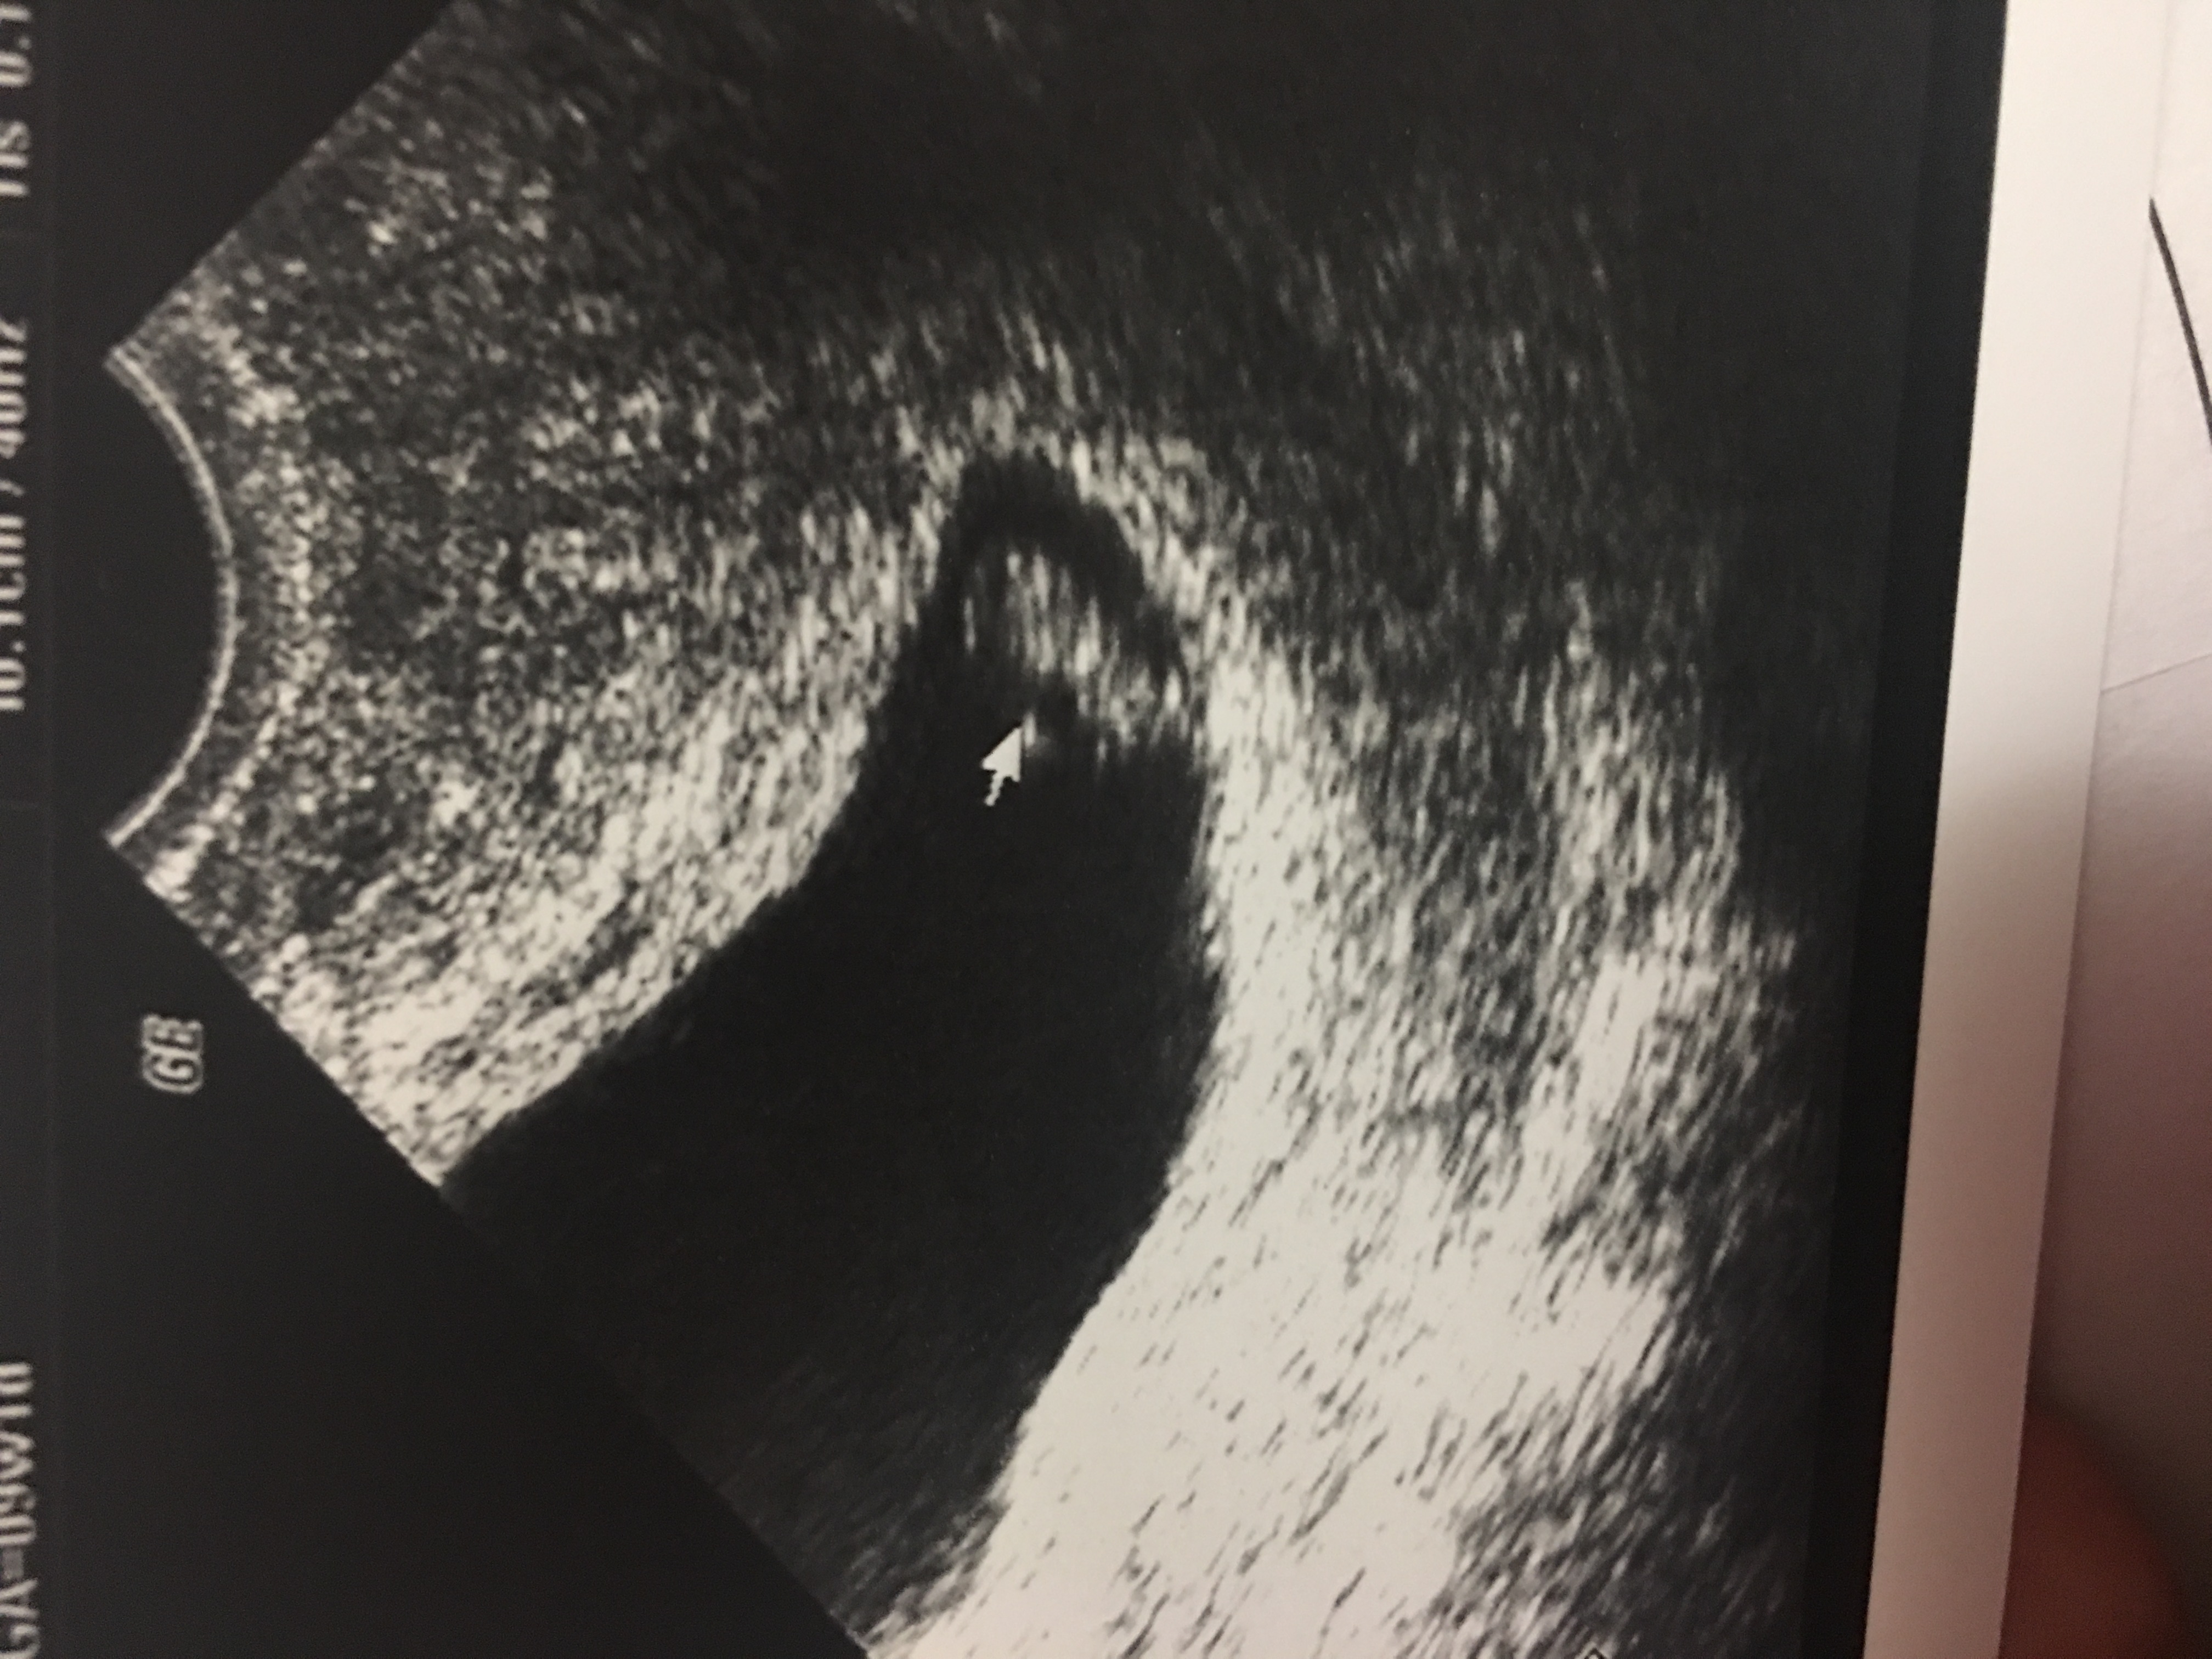

Any ramzy? Both are Vaginal u/s

Ramzi is completely debunked. No way to tell from these scans, sorry!

Thank u! I made a new post of new pics of my ultrasound of today plz hve a look